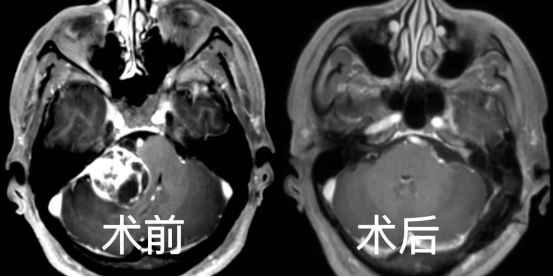

无独有偶,68 岁的胡爹爹在一年前发现左侧听力下降近伴有耳鸣,但却并未放在心上,最近通过其他人了解到可能是颅内长了肿瘤引起的才重视起来,来到我院神经外科专家门诊就诊。金胜昔教授给他做了行颅脑核磁共振之后,证实为左侧听神经瘤,肿瘤大小约 2.3*2.7*2.5 cm。术前电测听证实左侧无有效听力。通过完善术前检查后,再神经电生理、麻醉团队护航下历经约 6 小时完整切除肿瘤,术中面神经保护良好,术后病理提示为听神经鞘瘤。